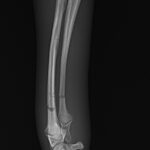

5ヶ月齢の小型犬がソファーからジャンプしたのちに橈骨骨折をしたとの事で、かかりつけ医より紹介受診されました。橈骨は遠位で階段状斜骨折を呈していました。遠位3穴にデザインされたストレートの1.5 Locking Plateをメインとし、橈骨の内側面からOrthogonal Plateにより骨接合術を行いました。しばらくは安静が必要です。